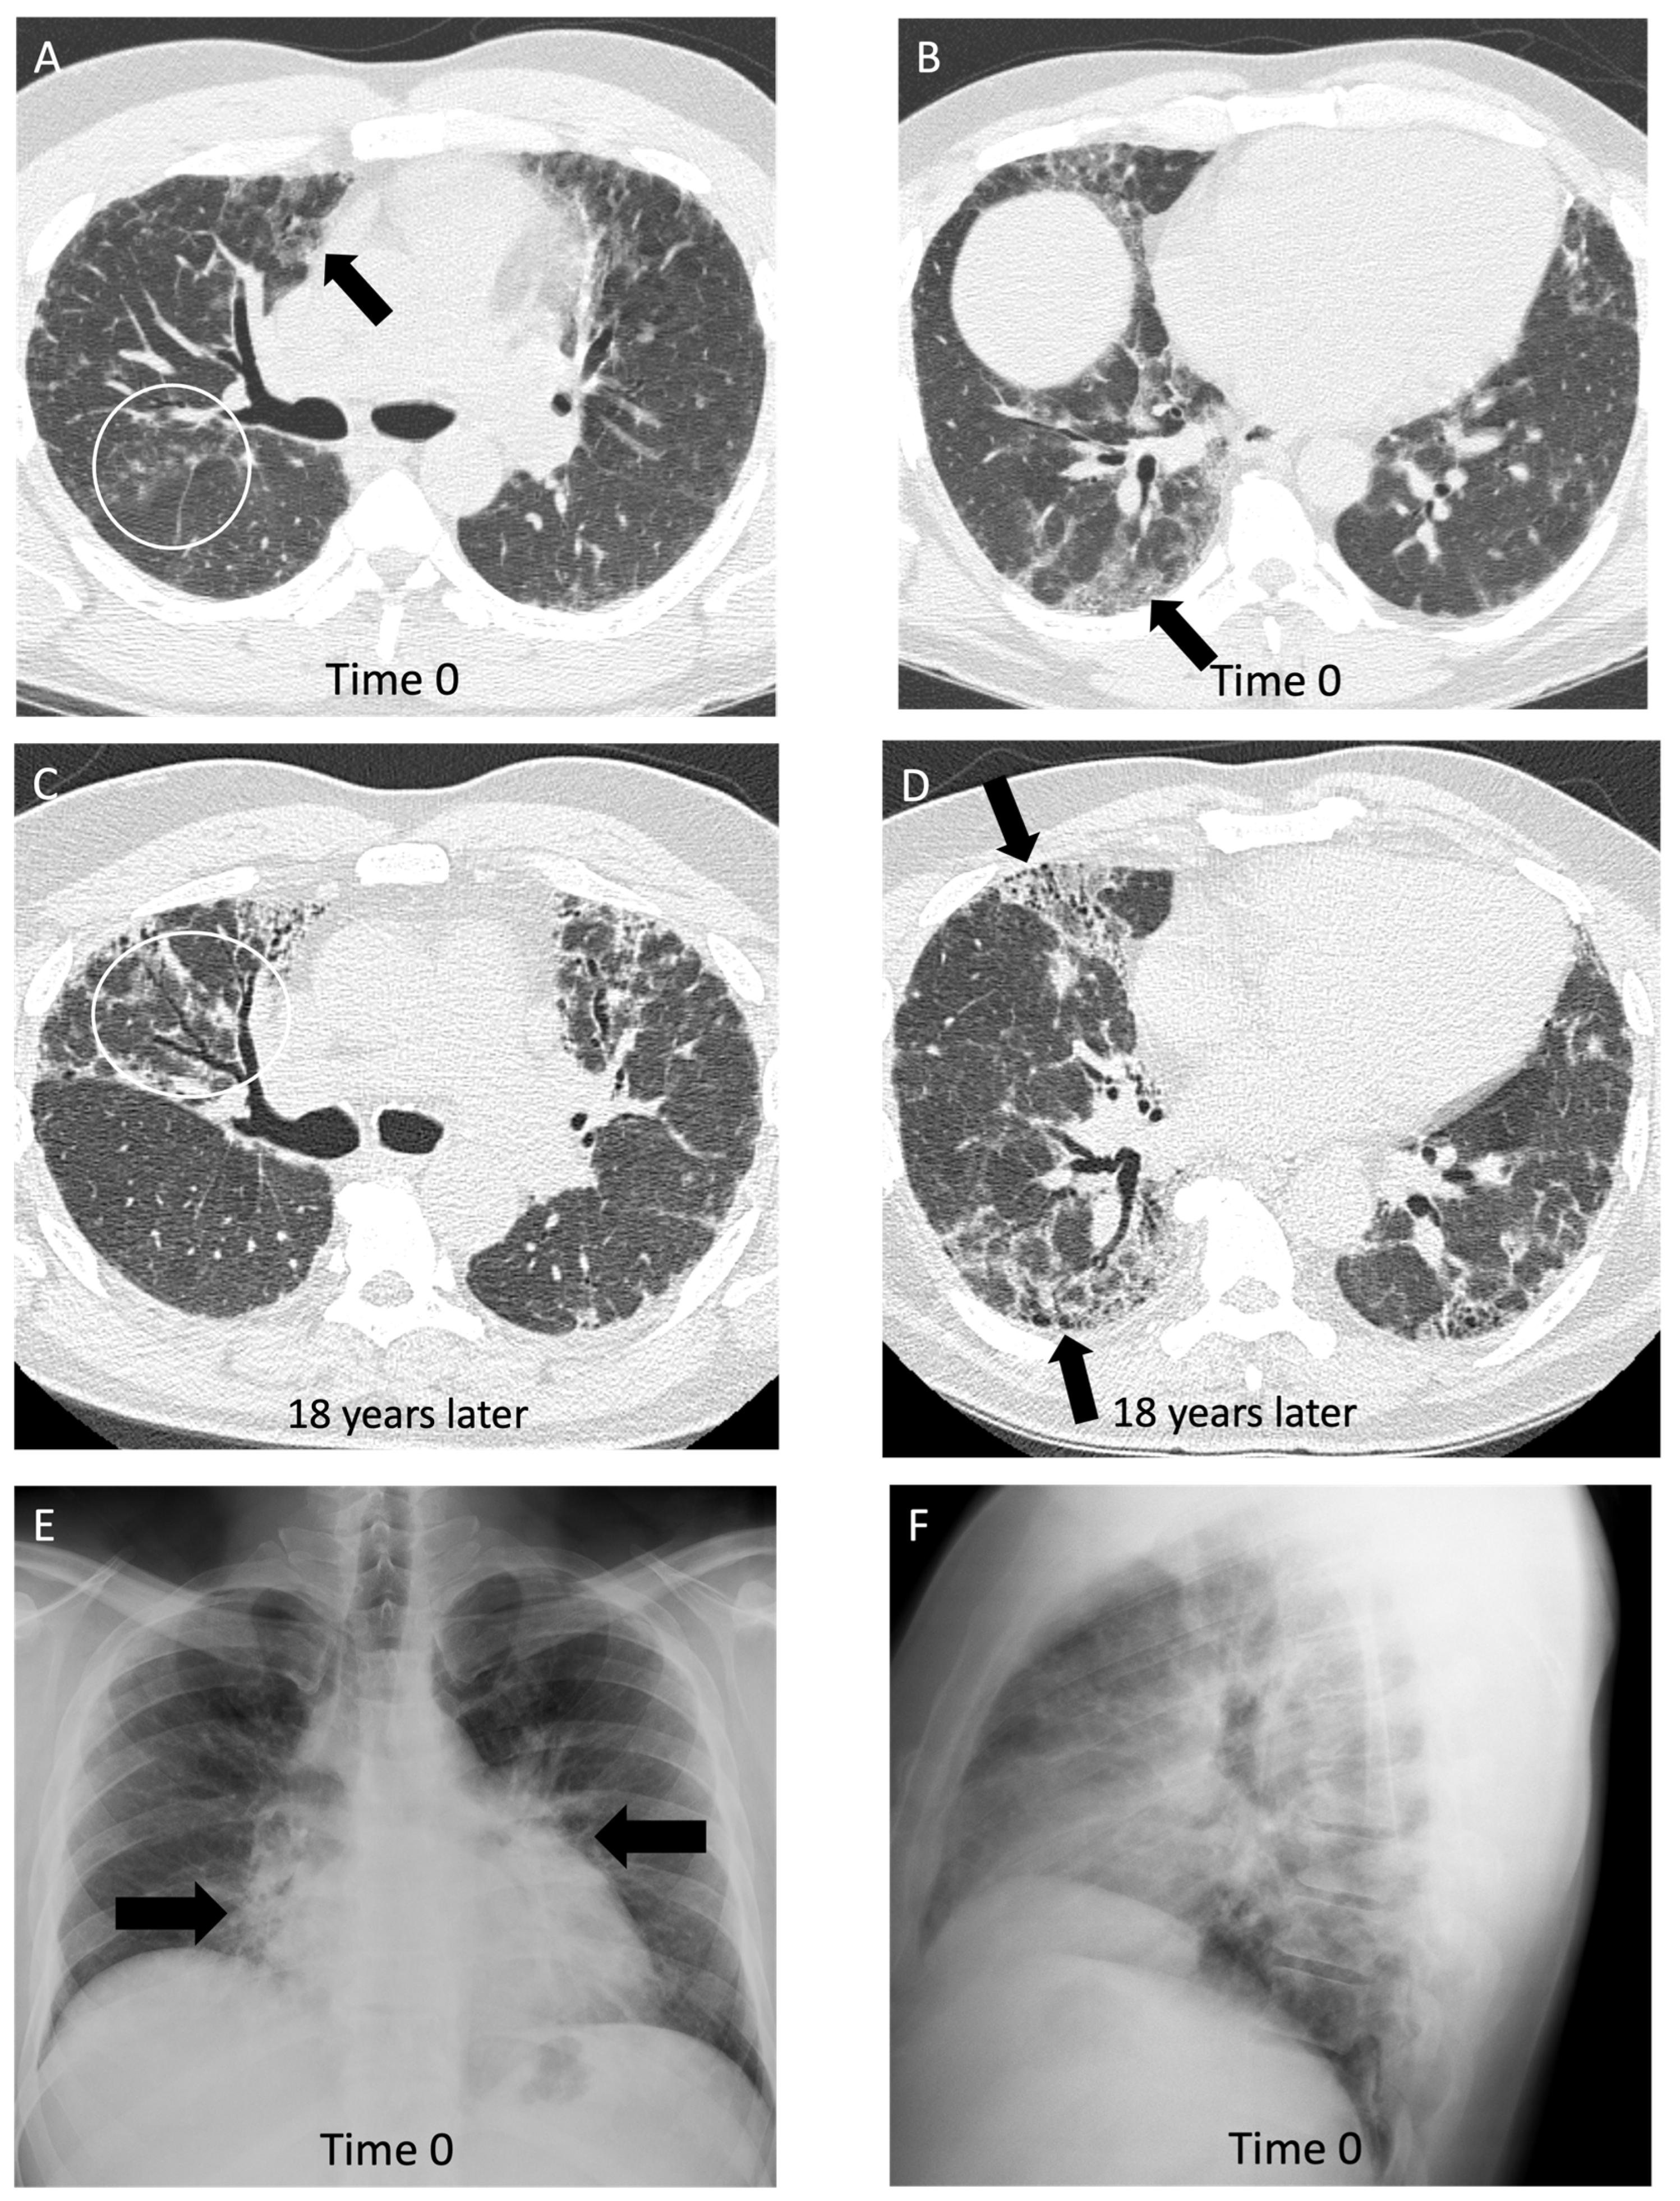

4.5. Other Pneumoconioses

5. Hypersensitivity Pneumonitis

| Hypersensitivity Pneumonitis | Non-fibrotic: diffuse ground glass opacities, nodules/consolidation present, centrilobular nodules [72] Fibrotic: peribronchiovascular fibrosis, small airway disease [67,72] | Difficult to differentiate by imaging only; evidence of ground glass opacities and air trapping along with bronchioalveolar lavage lymphocytosis aids diagnosis [66] |